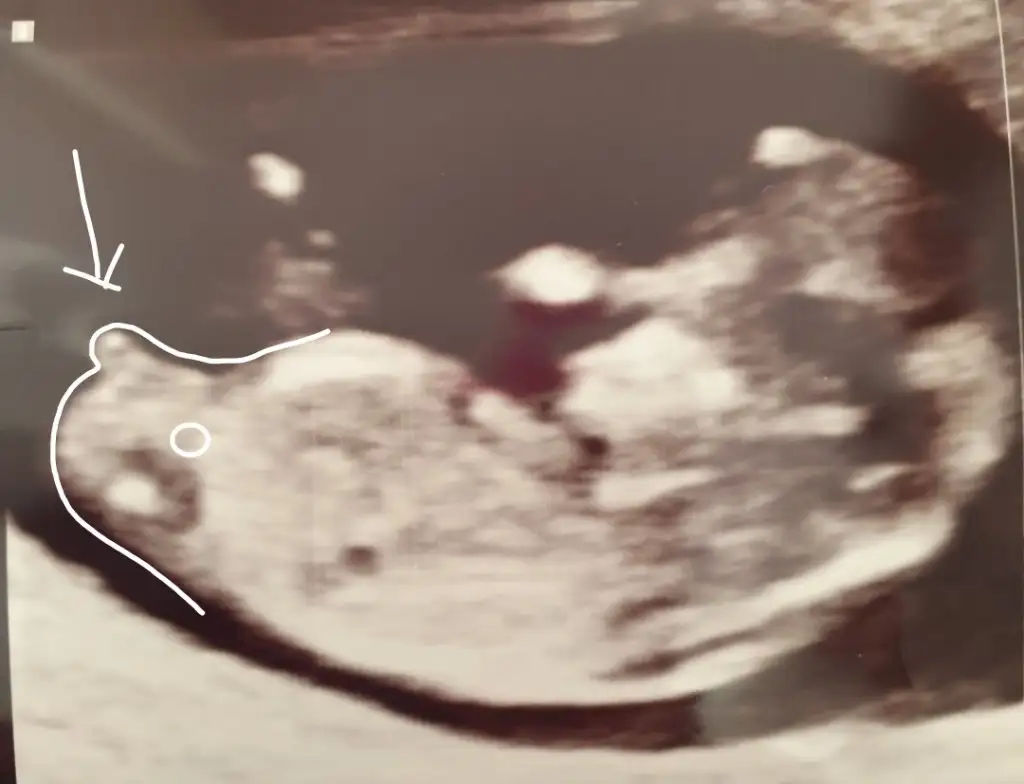

dr soylemeden siz gorun genital nub teorisi ( bebegin cinsiyeti)

İkra meyra cnm bakabilirmisin 11haftalık